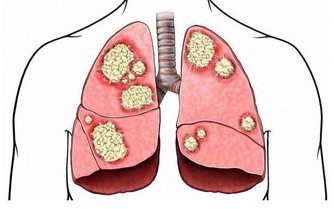

肝硬化:戒菸忌酒勤運動

肝臟是人體最大的代謝器官,我們吃進去的食物都需要肝臟進行合成、分解。在我國,每12個人中就有1人患肝病。

養肝護肝,要掌握正確觀念:

1、忌酒:酒精主要在肝臟被代謝,長期酗酒會傷害肝臟,脂肪肝最早出現,接下來會發展成肝纖維化、酒精性肝病,甚至轉變為肝硬化、肝癌。

2、控制肉食:多吃能增強肝臟解毒功能的食物,如花菜、西紅柿、黃瓜、苦瓜、胡蘿蔔等。

3、壞情緒會傷肝:發火傷肝,心情壓抑、鬱悶也會引起肝氣鬱結。城市生活節奏快、工作壓力大,很多人又缺少運動,找不到宣洩渠道,很容易受不良情緒影響,損害肝臟。

4、按時休息:躺下休息時,進入肝臟的血流量比站立時多數倍,有利於增強肝細胞功能,提高解毒能力。中醫認為,凌晨1-3點是肝經的“值班”時間,此時是養肝最佳時期。

5、勤運動:每天30分鐘的鍛煉,就能避免脂肪過度堆積,預防脂肪肝。